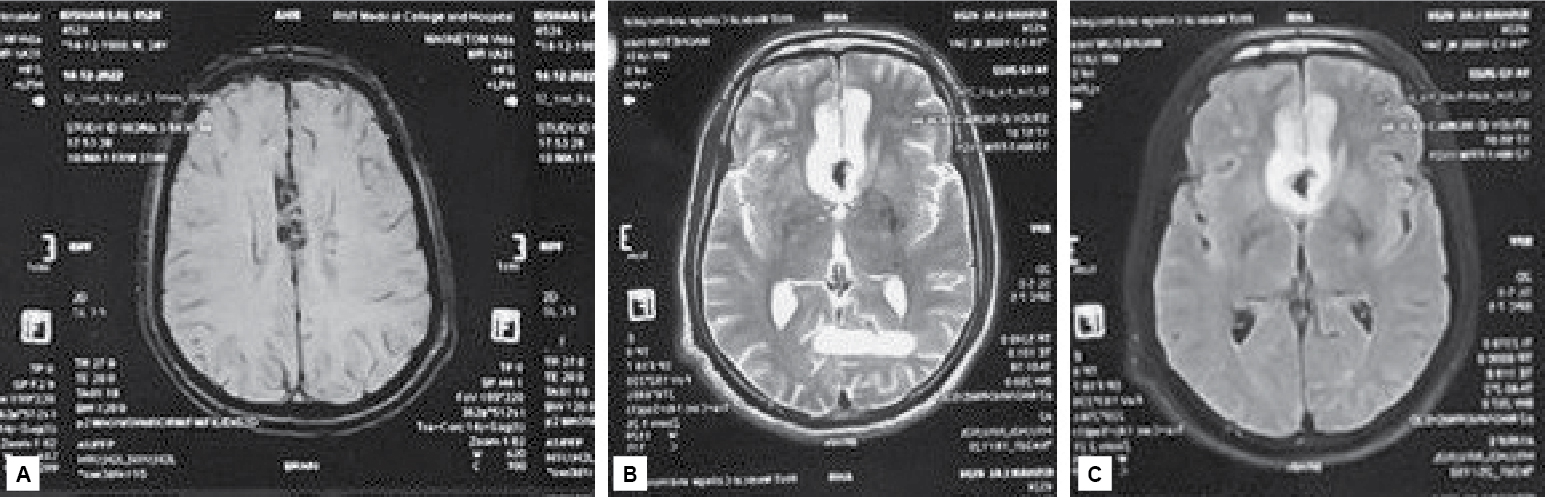

Auscultation of both lungs revealed normal vesicular breath sounds and no added sounds. Due to the acute febrile illness, a tentative diagnosis of malaria, dengue fever or scrub typhus was suspected. The patient was investigated. The complete blood count (CBC) was normal except for white blood cell (WBC) count, which was raised (24.5 × 103) on day of admission. It came down to normal on day 3 (10.3 × 103). His liver and renal function tests were absolutely normal (urea - 22.6 mg/dL, creatinine - 0.7 mg/dL, total bilirubin - 1.01 mg/dL, serum glutamic-oxaloacetic transaminase [SGOT] - 30 IU/L, serum glutamic-pyruvic transaminase [SGPT] - 25 IU/L, alkaline phosphatase [ALP] - 66 IU/L). Ultrasonography abdomen and chest X-ray were normal. The patient underwent specific investigations for acute febrile illness. Dengue IgG, IgM, NS1 antigen were negative, malaria parasite testing by slide and QBC (Quantitative buffy coat) test was found negative but scrub typhus IgM ELISA (enzyme-linked immunosorbent assay) was positive. Noncontrast computed tomography (NCCT) head was done and showed subdural hemorrhage along the falx. Magnetic resonance imaging (MRI) brain was done and showed early subacute subdural hemorrhage in parafalcine location in bilateral frontal region (Fig. 1). Patient was treated with IV mannitol, IV antiepileptic (phenytoin) along with symptomatic treatment in the form of antibiotic doxycycline, antimalarial, antipyretic and IV fluid, etc. On the third day of admission, improvement in sensorium was seen and the fever subsided. Hence, a diagnosis of scrub typhus with subdural hemorrhage was made.

Figure 1. SWI Image shows blooming along parafalcine location (A). T2W (B) and FLAIR (C) images show hyperintensity involving cortical as well as subcortical white matter in bilateral parafalcine frontal location.